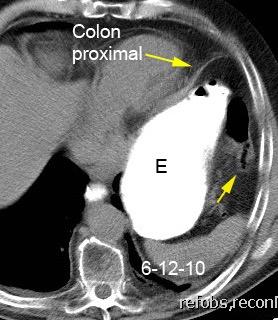

47. INTERPOSICIÓN CÓLICA DE CHILAIDITI

Interposición del colon entre hígado y diafragma

Más frecuente en pacientes con EPOC, cirrosis y ascitis

Incidencia.0,025%-0,28%.

Shinha T. Chilaiditi Syndrome. Intern Med. 2017

Vólvulo de flexura esplénica. Havenstrite KA. 1999

Hernia interna de colon transverso .hite JJ. 2002

Obstrucción cólica

Basile EJ et al. Chilaiditi Syndrome Presenting as Partial Colonic Obstruction. Cureus 2020